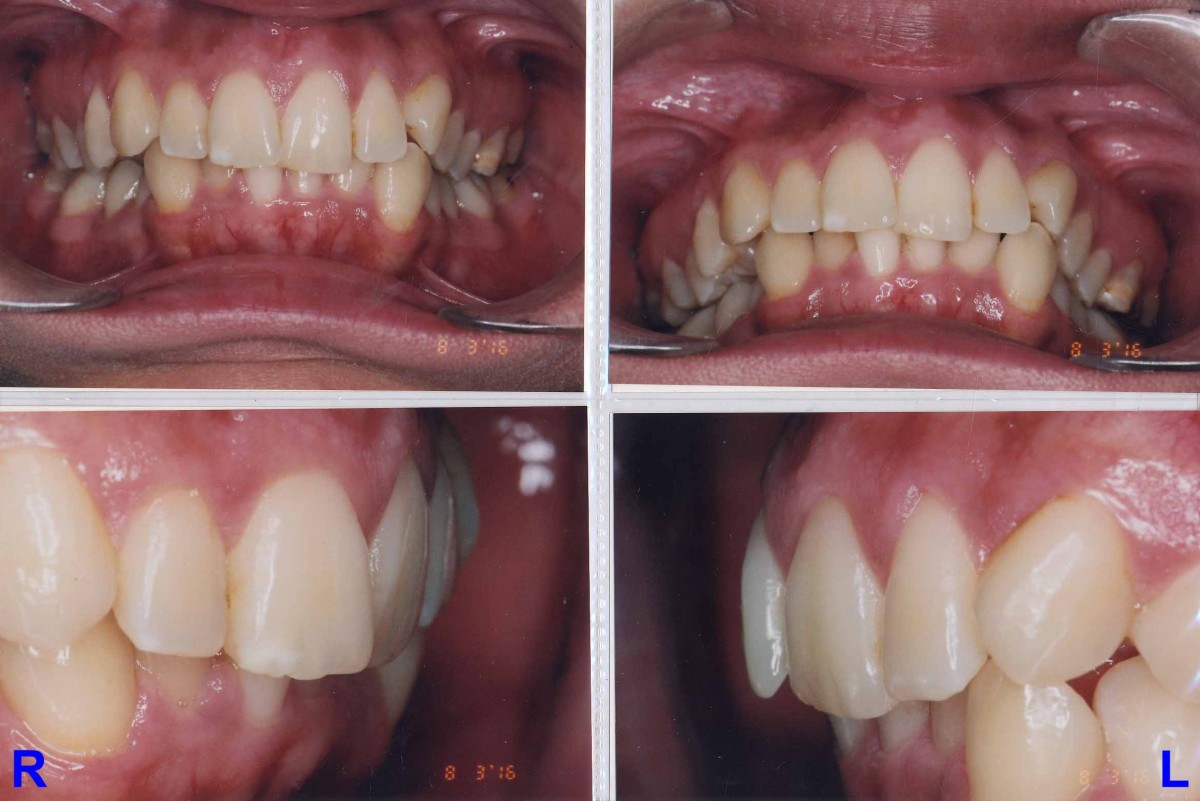

Pacient 23 ani. Extracție 1.4, 2.4, 3.5, 4.5, aparat ortodontic fix ceramic.